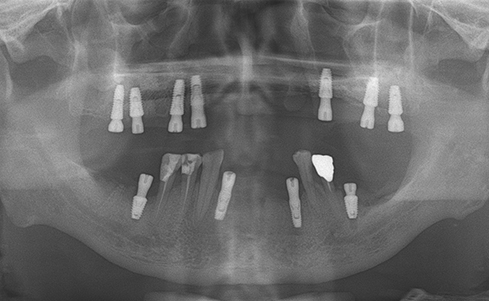

Fully edentulous clinical cases